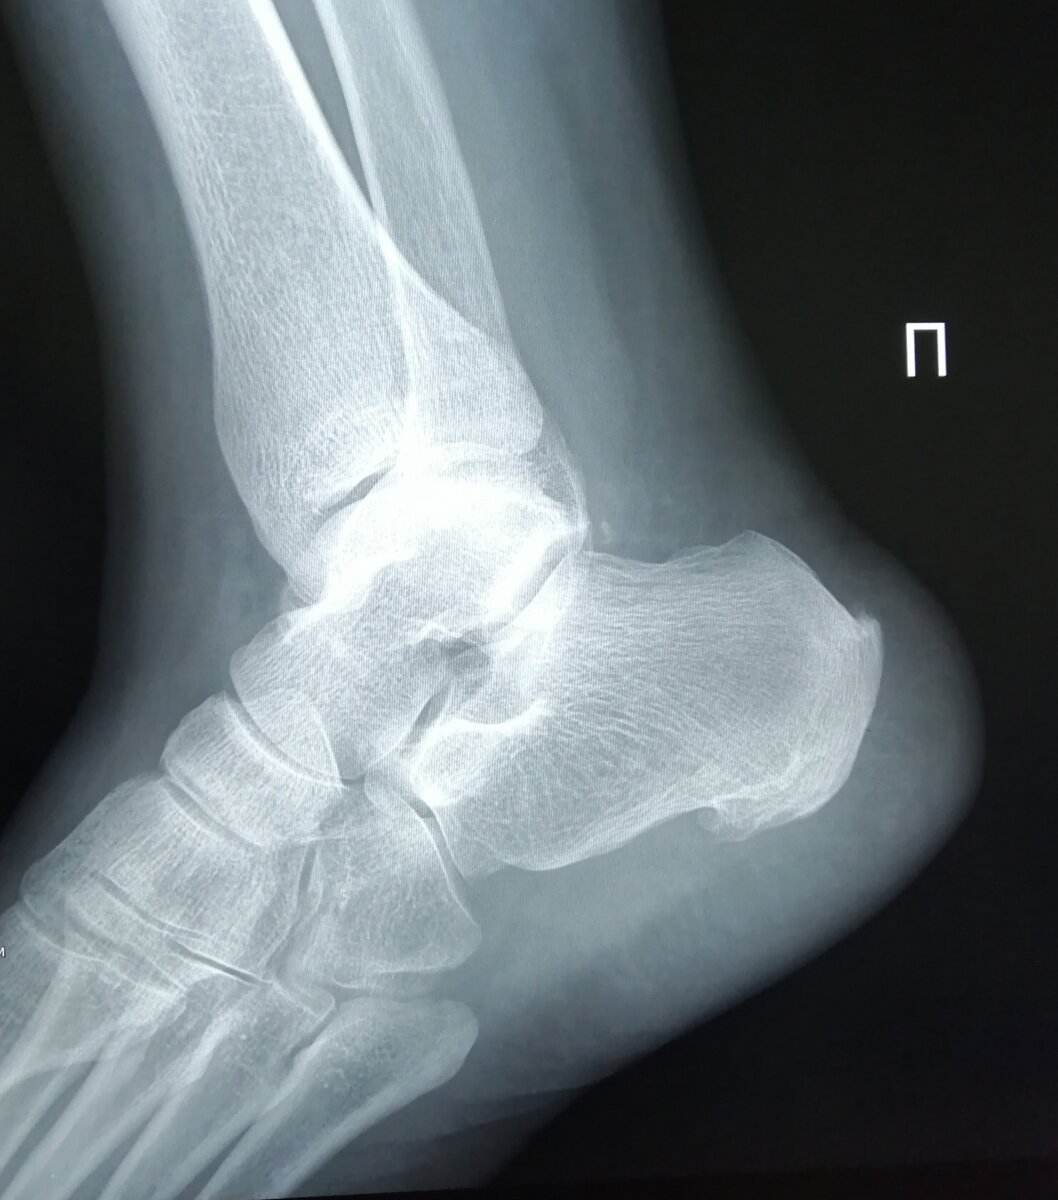

Плантарный фасциит, известный также как пяточная шпора, – это не просто неприятное заболевание, а настоящая проблема, способная ограничить жизнь человека. Врачи отмечают, что причиной боли служит воспаление плантарной фасции, прикрепленной к пяточной кости, исключительно на месте костного нароста. Постоянное давление на фасцию в ходе ходьбы вызывает серьезные болевые ощущения, которые могут напоминать острые колющие ощущения.